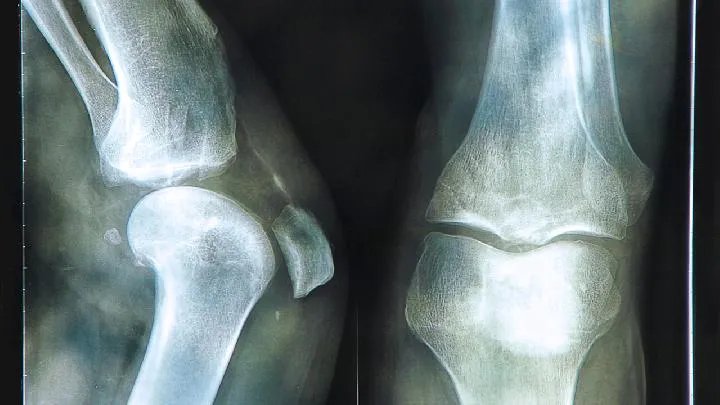

Ⅰ期股骨不变形,关节间隙正常,X线平片、CT多不能显示明显的骨质病变,称为X线前期。

Ⅱ期股骨不变形,关节间隙正常。T1加权是新月形边界清晰的不均匀信号,T2加权显示中等微高信号,周围不均匀微低信号,呈典型的双线征,位置基本和CT条状骨硬化一致。

Ⅲ期股骨变形、软骨骨折、塌陷、新月体形成。T1加权为带状低信号,T2加权表示中等或高信号,使关节积液进入软骨下骨折线的裂缝。